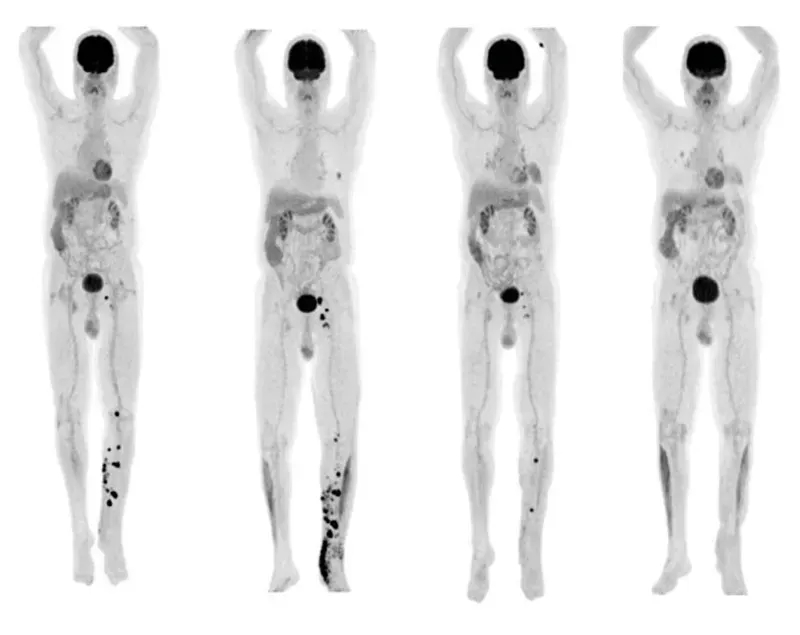

据《临床乳腺癌》杂志报道了一篇关于具有ETV6-NTRK3融合表达初次接受化疗的成人患者采用拉罗替尼治疗的临床研究,经6周治疗后患者PETCT显示肿瘤已消散大半。此外文章中还提及,乳腺分泌癌的肿瘤组织中超过90%的细胞都携带ETV6-NTRK3融合基因。所以,针对这种融合基因的靶向药物——拉罗替尼,对治疗分泌性乳腺癌有非常好的治疗效果。